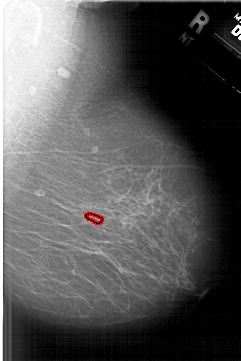

A_1633_1.LEFT_MLO

LEFT_MLO LINES 6256 PIXELS_PER_LINE 4576 BITS_PER_PIXEL 12 RESOLUTION 43.5 NON_OVERLAY

FILE: A_1633_1.RIGHT_MLO.OVERLAY

TOTAL_ABNORMALITIES 1

ABNORMALITY 1

LESION_TYPE CALCIFICATION TYPE PLEOMORPHIC DISTRIBUTION CLUSTERED

ASSESSMENT 4

SUBTLETY 3

PATHOLOGY BENIGN

TOTAL_OUTLINES 1

BOUNDARY